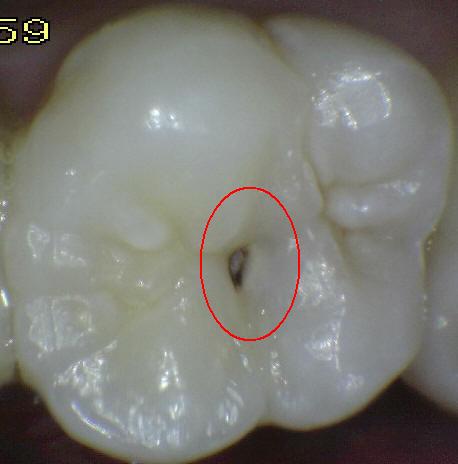

Código 3:

Ruptura localizada del esmalte debido a caries sin dentina visible

- El diente visto en estado

húmedo pueden tener una clara opacidad de caries (lesión de

mancha blanca)

y / o decoloración marrón de caries que es más ancha que la

fisura natural y la fosa, que no es consistente con la

apariencia clínica de esmalte sano. Una vez seco, se

observa una pérdida de estructura dental cariada en la

entrada, o dentro de la fosa o fisura . Esto se ve

visualmente como evidencia de desmineralización en la

entrada o dentro de la fisura o fosa, y aunque la fosa o

fisura puede aparecer sustancialmente más ancha que lo

natural, la dentina no es visible en las paredes o la base

de la cavidad ó discontinuidad .

En caso de duda, o

para confirmar la evaluación visual, la sonda de la OMS /

IPC / PSR puede ser

utilizada con cuidado a través de la superficie del diente,

para confirmar la presencia de una cavidad ( < 0,5mm.de

profundidad) al parecer limitada al esmalte . La

identificación de la cavidad se consigue deslizando el

extremo de la bola a lo largo de la fosa o fisura

sospechosa.